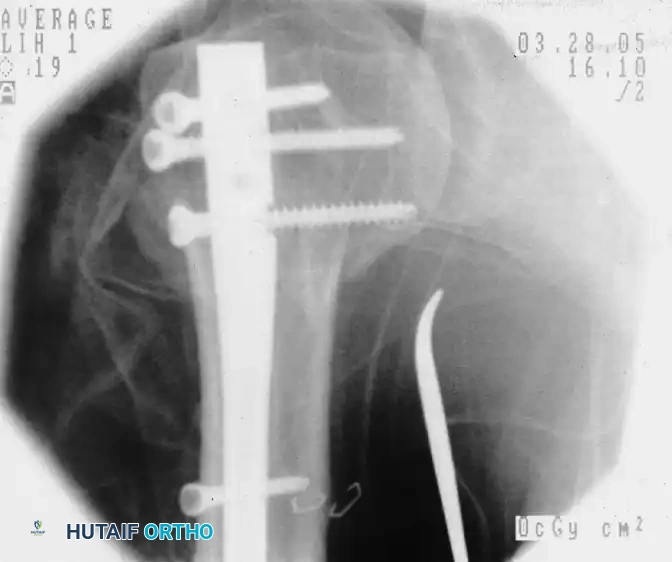

Preoperative fluoroscopic evaluation demonstrating a two-part surgical neck fracture of the proximal humerus, an ideal candidate for the anterolateral approach.

Placement of the initial guidewire into the proximal humerus, ensuring the correct entry trajectory for antegrade nailing.

Fluoroscopic confirmation after nail insertion and the placement of multi-planar proximal locking screws.